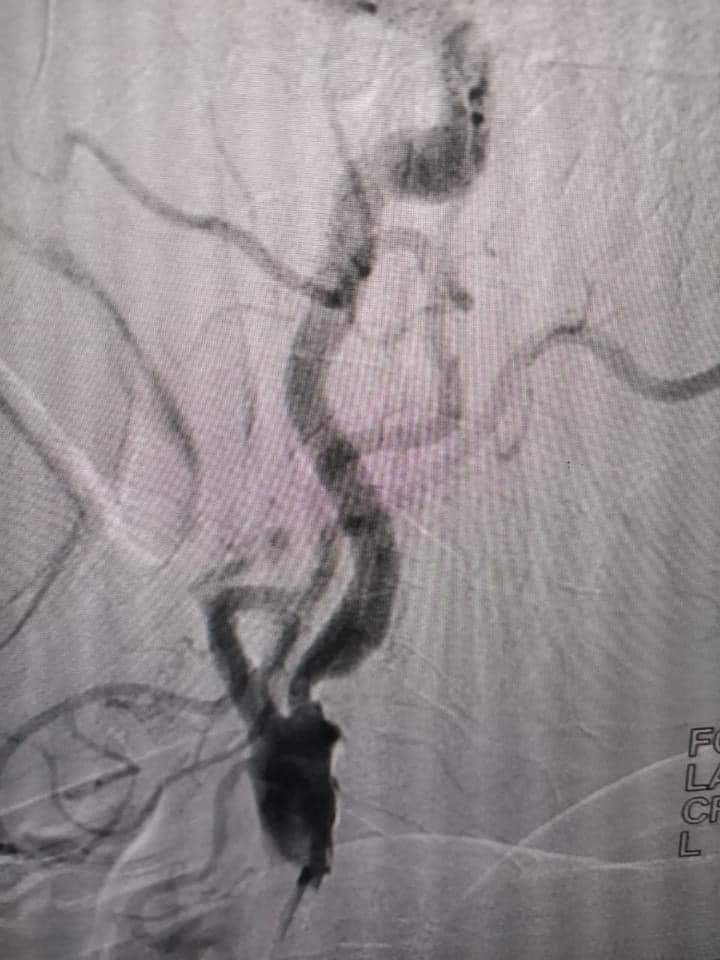

قسطرة مخية تشخيصي بمستشفى ملوي التخصصي بالمنيا

وأجرى الفريق الطبي أيضًا قسطرة مخية تشخيصية لثلاث حالات أخرى تعاني من نزيف في المخ.